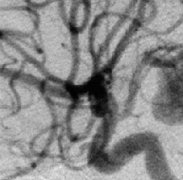

脑动脉瘤的定义、好发部位、诊断方法、预后影响因素,如何进行治疗和预防...

脑动脉瘤一旦破裂,凶险,且随时有再次出血的风险。到底什么人容易得脑动脉瘤?脑动脉瘤是怎么形成的?一文详细解答...